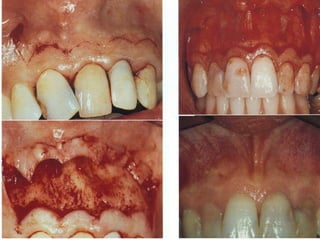

Healing following apical surgeries depend a large

extent on the soft tissue flap design. Different flap

designs have been advocated and used, depending

on the location and size of the peri-radicular lesion.

A new flap design, which used sub-marginal straight

incision was compared with intra-sulcular

rectangular/triangular flap and scalloped sub-

marginal flap. Post - Operative healing was

compared for swelling, alternation of colour,

recession of marginal gingival and extent of scarring.

It was found that sub-marginal straight horizontal

incision showed better healing with lesser

scarring. It is concluded that the new flap design

can provide an alternative.